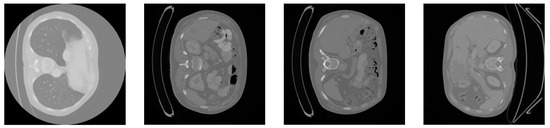

5.1. Dataset

5.2. Data Preprocessing